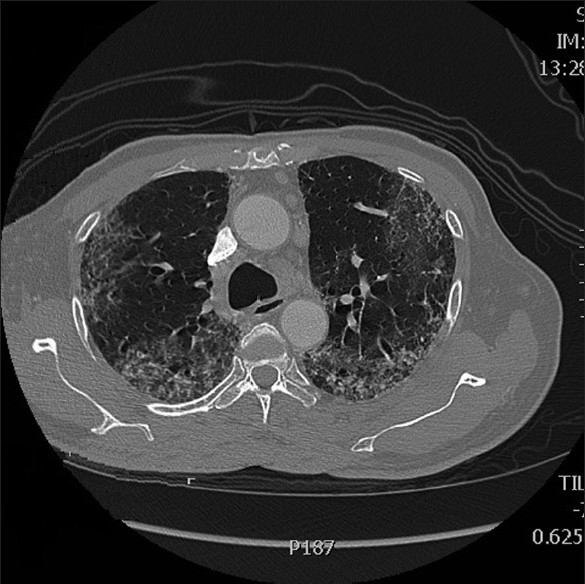

Adjuvant chemotherapy with oxaliplatin given at a dose of 130 mg/m2 intravenously on Day 1 of each three-week cycle, and capecitabine at a dose of 2000 mg/m2/day orally in two divided doses was given on Days 1–14 of each cycle.[4] The patient tolerated the initial cycle well; however, after the second cycle of the treatment, which was three weeks later, he developed progressive dyspnea and persistent cough despite having no history of any previous lung disease, and a pre-treatment chest X-ray was normal. A chest radiograph revealed diffuse bilateral interstitial infiltrates and an ABG performed showed significant hypoxia with PaO2 of 55 mmHg. A high resolution computed tomography (HRCT) scan [Figures [Figures11 and and2]2] showed bilateral alveolar infiltrates predominant in the bases. A trans-bronchial lung biopsy could not be performed as he was extremely breathless and hypoxic. He was commenced on 80 mg of methylprednisolone thrice a day. However his clinical condition began to deteriorate and within a week of starting steroids he succumbed to his illness.

| Figure 2 High resolution computed tomography scan 2